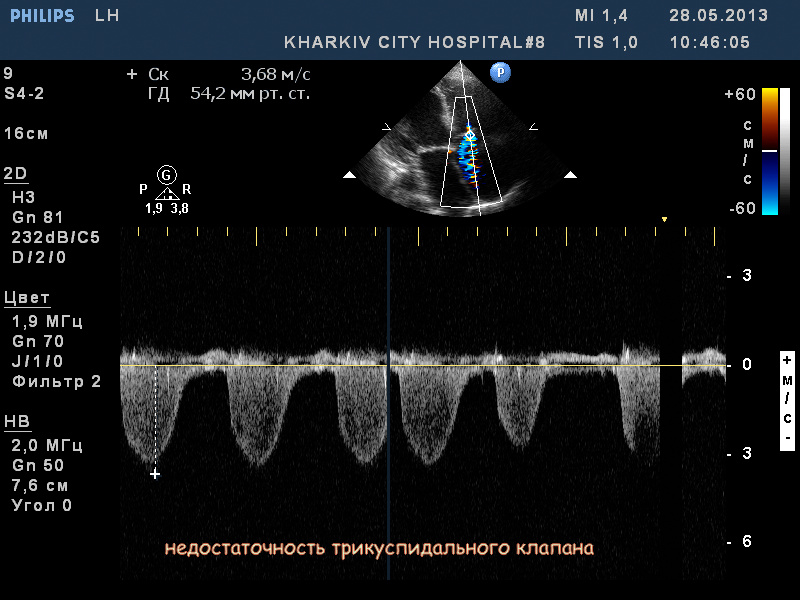

Пациентка 83 лет. Жалобы на сильную одышку в теч. последнего месяца.

кальциноз створок АК, дилатация левого предсердия, правых полостей, выраженная недостаточность ТК и клапана ЛА, гипертрофия левого желудочка. Дополнительные косые хорды левого желудочка. Высокая ЛГ (АТ/ЕТ- 0.20 Рсред. ЛА-69мм рт.ст.).